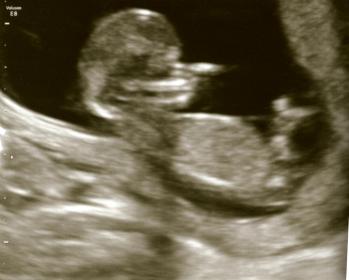

Any guesses? Thank you in advance!!!

No nub.

I don't see a nub either

Leaning boy

I can't see a nub in the picture. Doesn't necessarily mean girl, just not a great shot...

no nub but a boyish skull